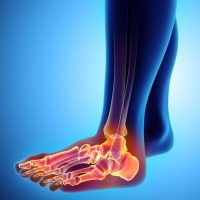

Прилагайки една от най-ефективните терапии за лечение на сухожилия и лигаменти, благодарение на огромния опит и екпертиза на доктор Кавалино ние сме способни да помагаме на хора из цяла България да спрат да чувстват болка.